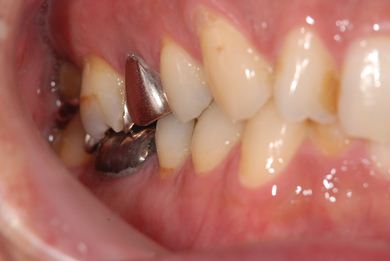

抜歯即日スピードインプラント治療

| 主訴 | 前歯が折れていてないので、インプラント治療を希望。 | ||||||||||||||||||||||||||||||||

| 治療内容 | インプラント1本(抜歯即日スピードインプラント)、ハイブリッドセラミッククラウン1本 | ||||||||||||||||||||||||||||||||